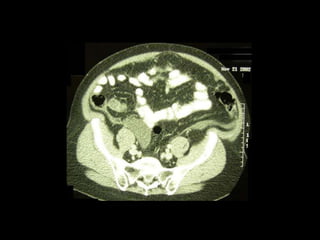

Pseudomyxoma peritonei (PMP) is a rare condition characterized by gelatinous ascites resulting from the rupture of appendiceal mucinous tumors, leading to significant abdominal complications. The incidence is approximately 2 cases per million per year, with a predominance in females, and diagnosis often relies on imaging techniques like ultrasound and CT scans. Effective treatment involves cytoreductive surgery combined with hyperthermic intraperitoneal chemotherapy (HIPEC) to manage disease progression and improve outcomes.